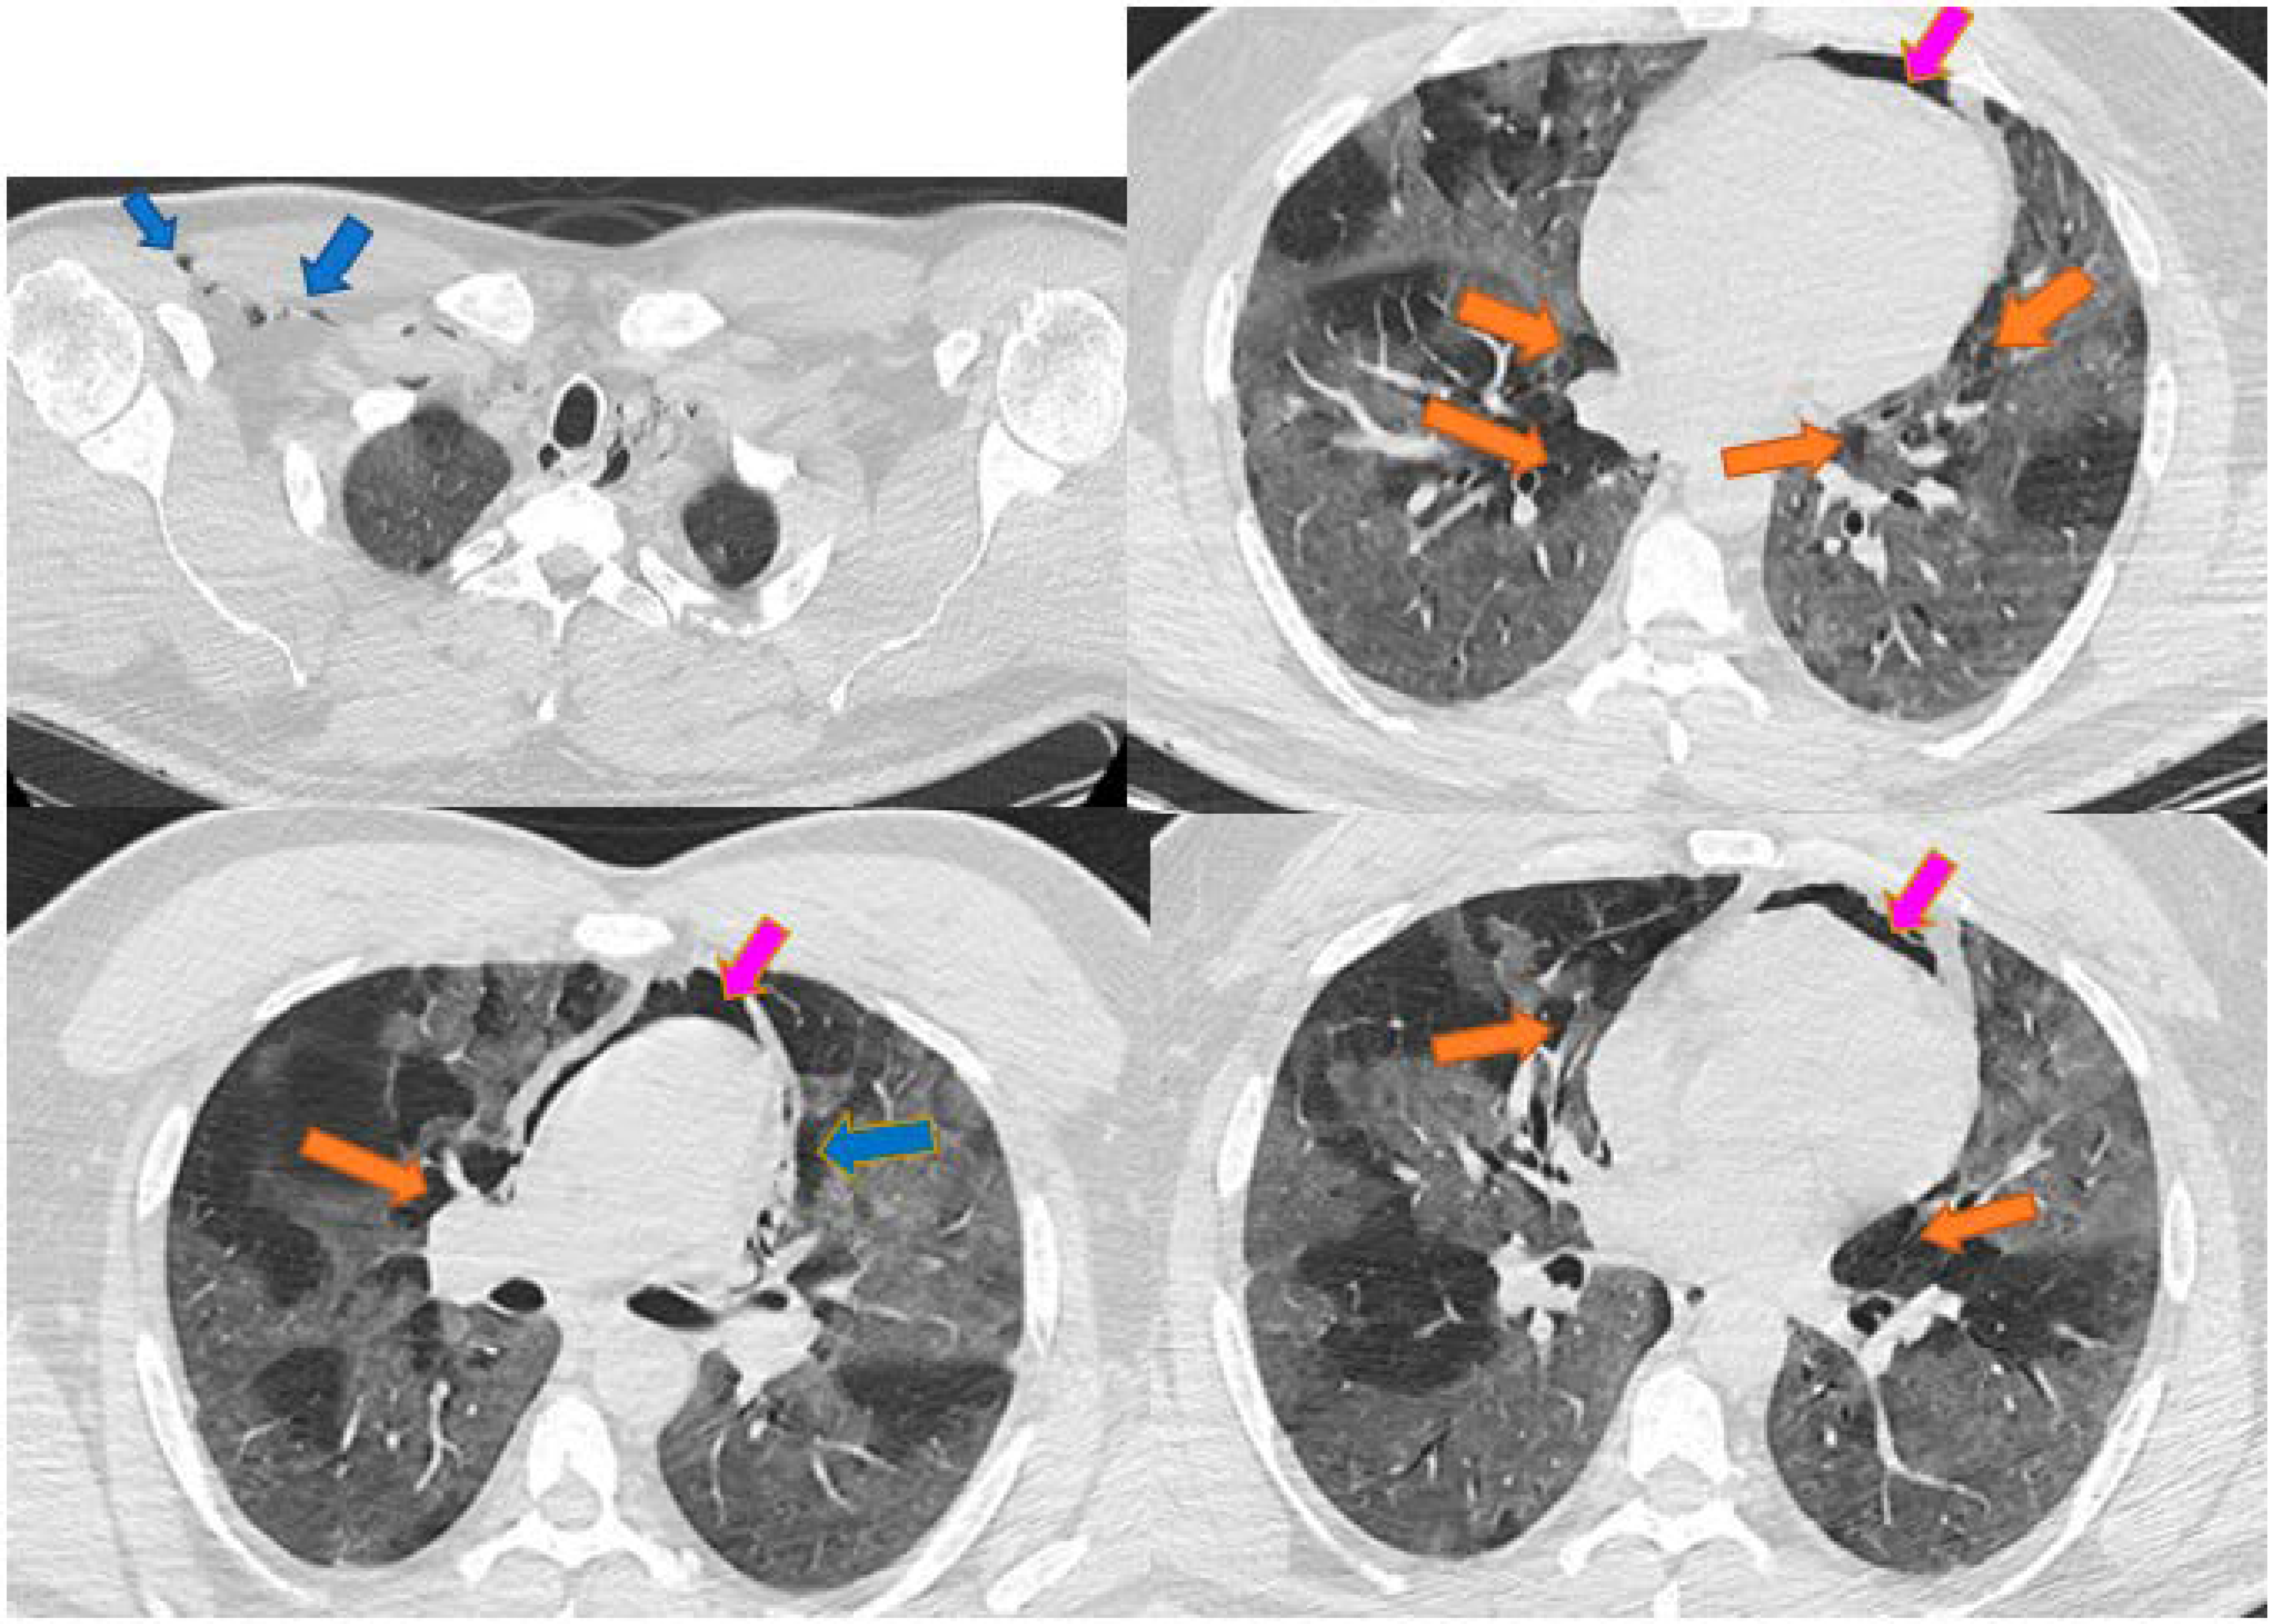

Spontaneous Pneumomediastinum, Pneumothorax, Pneumopericardium and Subcutaneous Emphysema—Not So Uncommon Complications in Patients with COVID-19 Pulmonary Infection—A Series of Cases